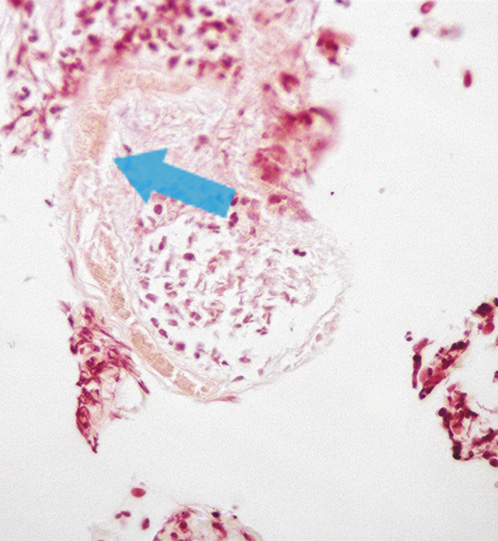

Four weeks later, despite treatment with pantoprazole, the patient complained of persisting abdominal pain. Evaluation of the gastric ulcer biopsies identified fragments of partially destroyed parasites with inflammatory infiltrates and fibrinogranulocytic exudate, indicative of S. stercoralis (Fig. 4). In the multiple biopsies evaluated there was no evidence of malignancy or Helicobacter pylori.

Fig. 4: Hematoxylin-eosin stain of the biopsy sample from the gastric ulcer showing a partially destroyed Strongyloides stercoralis nematode.

Considering the differential diagnosis of the gastric ulcer, in the absence of risk factors for stress ulcer and persisting pain despite proton pump inhibitors, with biopsies ruling out malignancy or H. pylori and having recognized S. stercoralis in the histopathological examination, the most likely etiological diagnosis was strongyloidiasis. Moreover, the patient had significant weight loss with folate and iron deficiencies representing a malabsorption state, which is a manifestation of strongyloidiasis. A PCR-based assay was performed in repeated stool samples and was positive for S. stercoralis.Serological tests using ELISA were positive and consistent with the diagnosis of strongyloidiasis. Treatment with ivermectin 200 μg/kg was administered on 2 consecutive days and pantoprazole was interrupted. On reevaluation 6 weeks after the ivermectin treatment, the patient was asymptomatic, had gained weight, folic acid and iron levels were within the normal range, parasitological stool examinations were negative, and the upper endoscopy showed complete ulcer healing. This significant improvement after ivermectin treatment is consistent with the etiology of the gastric ulcer being caused by the parasite.